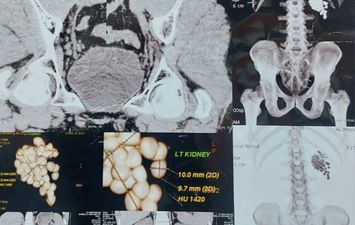

إنجاز طبي بقنا: فريق جامعي يزيل 58 حصوة من كلية مريض عبر منظار متقدم

أعلنت مستشفيات قنا الجامعية، نجاح فريق طبي متخصص بمستشفى المعبر الجامعي، في إجراء عملية دقيقة لاستخراج 58 حصوة من الكلية اليسرى لمريض يبلغ من العمر 40 عامًا، وذلك باستخدام أحدث تقنيات مناظير الكلى المتقدمة.

وأوضح الأستاذ الدكتور مصطفى عبد الرازق رئيس قسم المسالك البولية، أن المريض وصل وهو يعاني من آلام متكررة وارتفاع في نسبة الأملاح، وبفحصه تبيّن وجود عدد كبير من الحصوات المتجمعة في حوض الكلية اليسرى، ما استدعى التدخل الجراحي حفاظًا على وظائف الكلية.

وأشار إلى أنه تم تجهيز المريض وإخضاعه للتخدير العام، ثم البدء في العملية من خلال فتحة صغيرة لا تتجاوز سنتيمترًا واحدًا للوصول إلى الكلية، قبل تفتيت الحصوات باستخدام تقنيات التفتيت الهوائي والليزر تبعًا لطبيعة كل حصوة.

واستمرت العملية نحو ساعتين، تمكن خلالها الفريق الطبي من إزالة جميع الحصوات والتأكد من تنظيف حوض الكلية بالكامل، مع تركيب أنبوب تصريف مؤقت لضمان خروج السوائل بصورة آمنة.